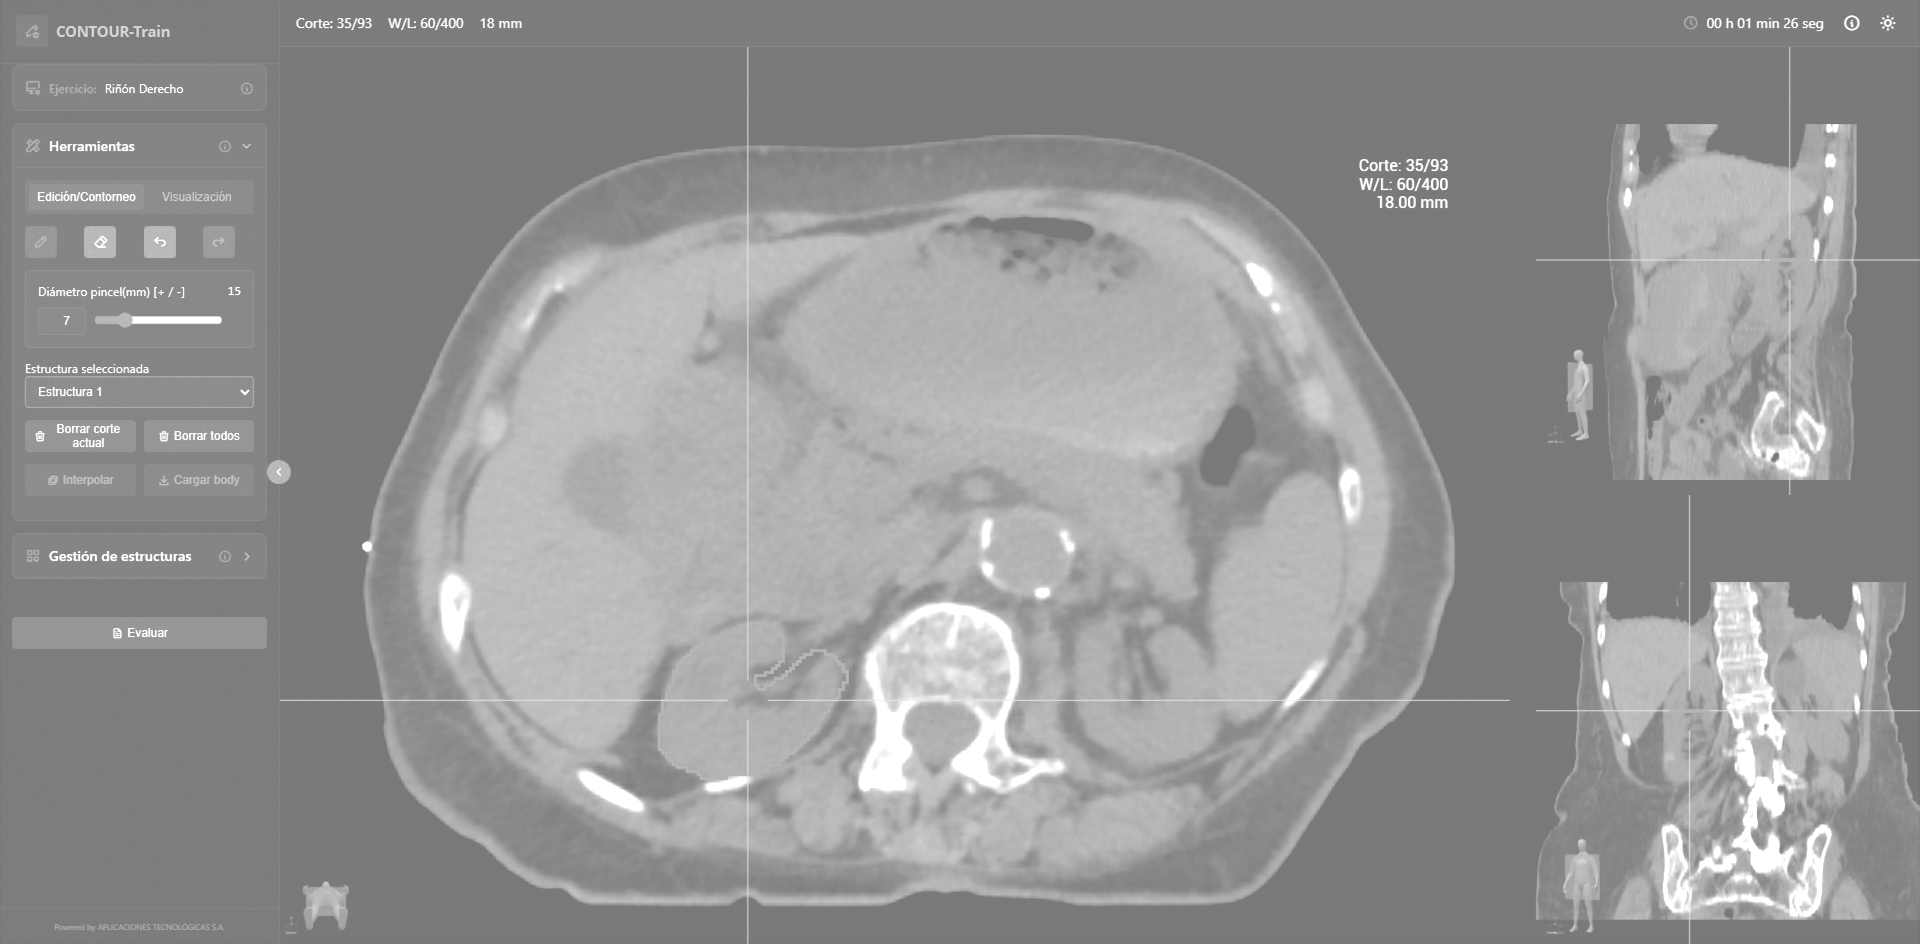

CONTOUR-Train

Formación avanzada: delimitando el cáncer, maximizando la eficacia.

Curso de contorneo para residentes de Oncología Radioterápica

Formación especializada para Oncólogos Radioterápicos

Herramienta formativa para aprender la correcta delimitación de lesiones tumorales y órganos de riesgo. Abarca las distintas patologías existentes en oncología radioterápica.